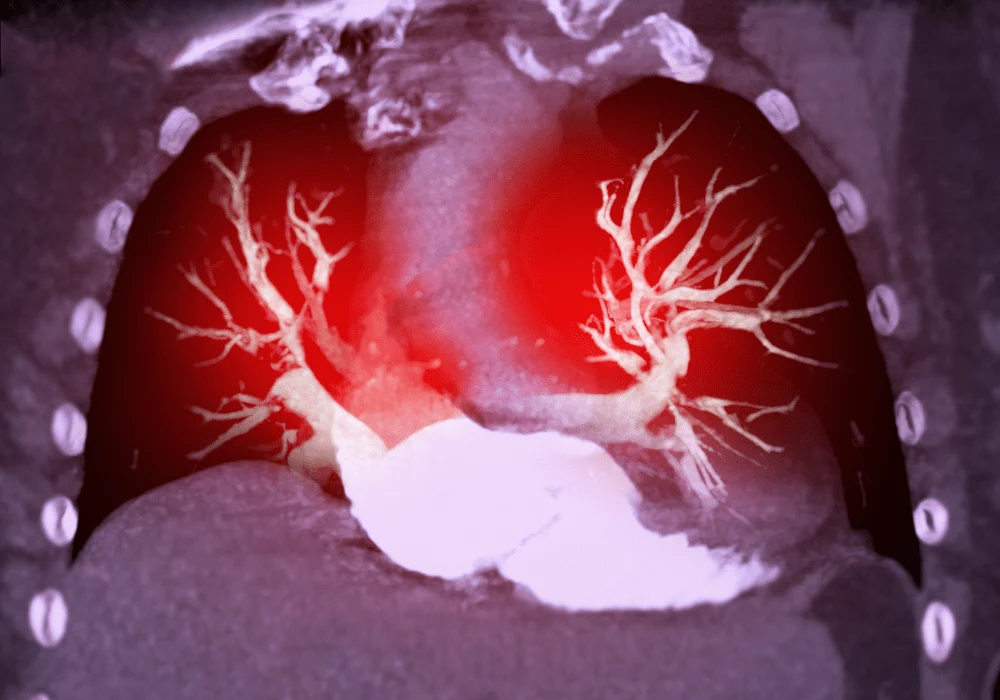

Spectral computed tomography (CT) has transformed diagnostic imaging, particularly in pulmonary angiography, where precision is critical. The use of dual-energy CT pulmonary angiography (DECT-PA) allows for improved visualisation of vascular structures and embolisms. Recent advancements in deep learning spectral reconstruction (DLSR) have further enhanced image quality by reducing noise and improving contrast resolution. A recent study has explored the comparative performance of standard versus strong DLSR in DECT-PA, focusing on image quality and diagnostic performance.

The integration of DLSR in DECT-PA imaging offers significant improvements in image quality. Strong DLSR algorithms reduce image noise more effectively than standard DLSR, particularly in low-energy virtual monochromatic images (VMIs) where noise levels are often elevated. The ability to reduce noise in low-energy VMIs is especially crucial, as these images provide superior contrast resolution, aiding in the detection of vascular abnormalities and pulmonary embolisms. Strong DLSR results in higher signal-to-noise ratios (SNR) and contrast-to-noise ratios (CNR) across multiple anatomical regions. This enhanced clarity benefits the detection of pulmonary embolisms, especially in low-contrast scans, by providing clearer differentiation between vascular structures and clot formations.

A comparative study involving 70 patients evaluated the performance of standard versus strong DLSR in DECT-PA imaging. The study revealed that strong DLSR consistently outperformed standard DLSR in both quantitative and qualitative assessments. Quantitative metrics, such as SNR and CNR, were significantly higher in cardiovascular and solid organ imaging with strong DLSR, with noise reduction reaching up to 15%. These improvements were evident across a range of energy levels, highlighting the robustness of the strong DLSR algorithm.

Qualitative analysis was conducted by expert radiologists who independently reviewed the image sets without knowledge of the reconstruction technique used. Both standard and strong DLSR produced diagnostically acceptable images, but strong DLSR provided a subtle yet measurable enhancement in clarity and detail. This improvement was especially noted in regions prone to higher noise, such as the pulmonary arteries and areas near the heart where motion artefacts can impact clarity. The reduction in image noise and improved contrast were consistently noted as key factors contributing to improved diagnostic confidence with strong DLSR.